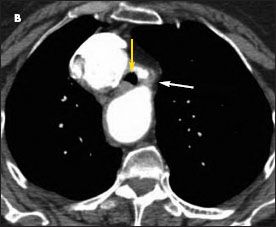

A high-resolution CT scan of the chest confirmed a right-sided aortic arch; a small ductus diverticulum was also noted just distal to the origin of the left subclavian artery, which was causing near circumferential compression of the trachea (Figure 2). Tracheal diameter at the thoracic inlet measured 1.1 cm, whereas maximal tracheal width at the level of greatest narrowing was 4 mm. Tracheal stenosis was strongly suspected.

Figure 2 – A highresolution CT scan of the chest confirmed the finding of a right-sided aortic arch and revealed marked narrowing of the trachea (B, yellow arrow) and a fibrous band between the left subclavian artery and the descending aorta (B, white arrow). The tracheal narrowing was apparent when comparing the view at the level of stenosis (B) with the cephalad (A) and caudad (C) views.